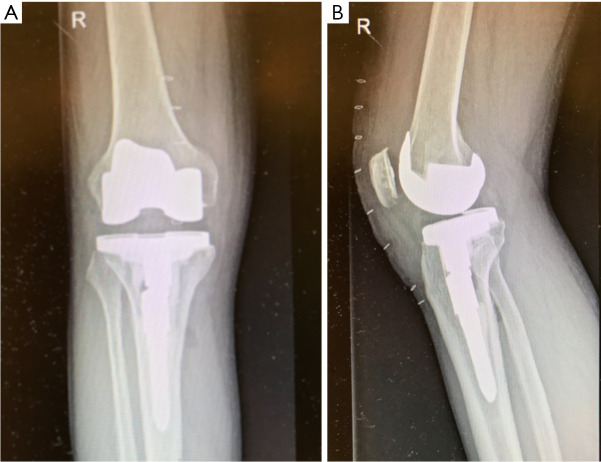

Abstract Image